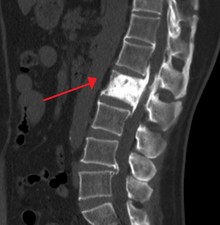

"This 92 year-old male patient presented for assessment of sudden inability to move half their body. An incidental finding was marked thickening of the calvarium. The diploic space is widened and there are ill-defined sclerotic and lucent areas throughout. The cortex is thickened and irregular. The findings probably correspond to the “cotton wool spots” seen on plain films in the later stages of Paget’s disease." | |